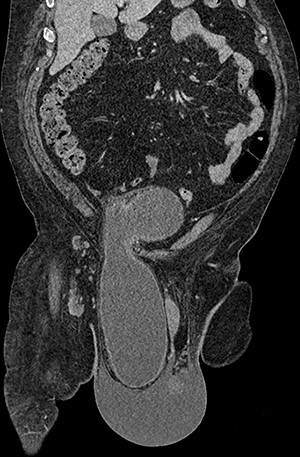

Computed tomography (CT) scan of the abdomen and pelvis with contrast revealed a large right indirect inguinal hernia containing a significant portion of the bladder within the scrotum (Figs 1–3). There was associated bilateral hydronephrosis and hydroureter, and significant scrotal oedema seen within the soft tissues.

(A and B) Axial CT images of the abdomen and pelvis demonstrating the bladder herniating out of the inguinal canal into the scrotum.